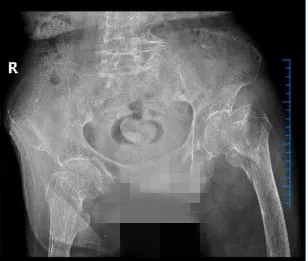

2025年3月,武寧(níng)縣總(zǒng)醫院人民醫院院區骨科團隊(duì)以精湛的技術和多學科協作模式,為一名(míng)104歲超高齡股骨粗隆間骨折(shé)患者成功實施微創(chuàng) Intertan 內固定術。這一壯舉不僅挽(wǎn)救了患者的生(shēng)命,更標誌著醫院在老年骨(gǔ)創傷救治領域取得了新的突破。

患者陳奶奶,今年104歲,因不慎跌倒導致左(zuǒ)側股骨粗隆間粉碎(suì)性骨折。她既往(wǎng)患有重度骨質疏鬆、低蛋白血症、心房(fáng)顫動、心功能不全、慢性阻塞性肺病(COPD)、脊柱畸形等多項基礎疾(jí)病。髖部(bù)骨折被稱為“人(rén)生最後(hòu)一次骨折”,保守治療會導致患者(zhě)長期臥(wò)床,不僅承受劇烈疼痛,還容易引發深靜脈血栓、肺部感染、褥瘡等嚴重並發症,死亡(wáng)率極高。

骨科團隊憑借豐(fēng)富的臨床經驗和先進的技術手(shǒu)段,采用國際領先的Intertan髓內釘係統,通過微創小切口完成複位固定。該係統具有雙螺釘設計,形成(chéng)更強的抗旋轉能力,提供更高的穩定性;同時利用滑動(dòng)加(jiā)壓(yā)原理,促進骨痂形成,顯著減少術後並發症的發生。手術(shù)僅曆時30分鍾,術中出血不到50毫升,極(jí)大地降低了(le)手術風險。